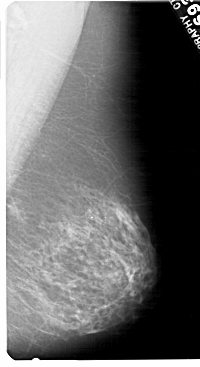

A_1480_1.LEFT_CC

LEFT_CC LINES 5491 PIXELS_PER_LINE 3001 BITS_PER_PIXEL 12 RESOLUTION 43.5 OVERLAY

FILE: A_1480_1.LEFT_CC.OVERLAY

TOTAL_ABNORMALITIES 1

ABNORMALITY 1

LESION_TYPE CALCIFICATION TYPE PLEOMORPHIC DISTRIBUTION CLUSTERED

ASSESSMENT 4

SUBTLETY 1

PATHOLOGY BENIGN

TOTAL_OUTLINES 1

BOUNDARY